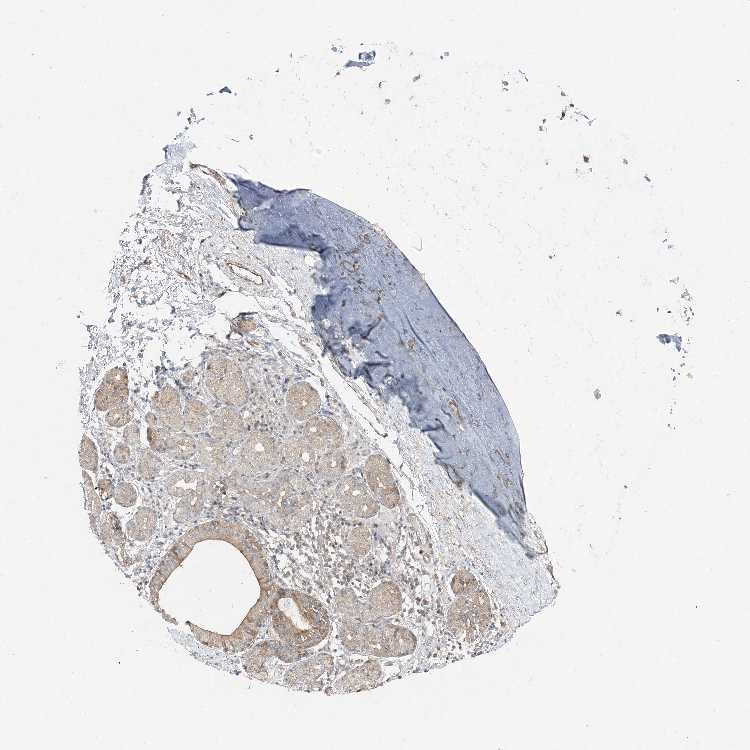

SOFT TISSUE 1 - Antibody stainingi

Antibody staining in the annotated cell types in the current human tissue is reported as not detected, low, medium, or high, based on conventional immunohistochemistry profiling in selected tissues. This score is based on the combination of the staining intensity and fraction of stained cells.

Each image is clickable and will lead to virtual microscopy that enables deeper exploration of all samples and also displays staining intensity scores, fraction scores and subcellular localization as well as patient and tissue information for each sample.

Antibody HPA036508

Chondrocytes Low

Fibroblasts Medium

Peripheral nerve Medium